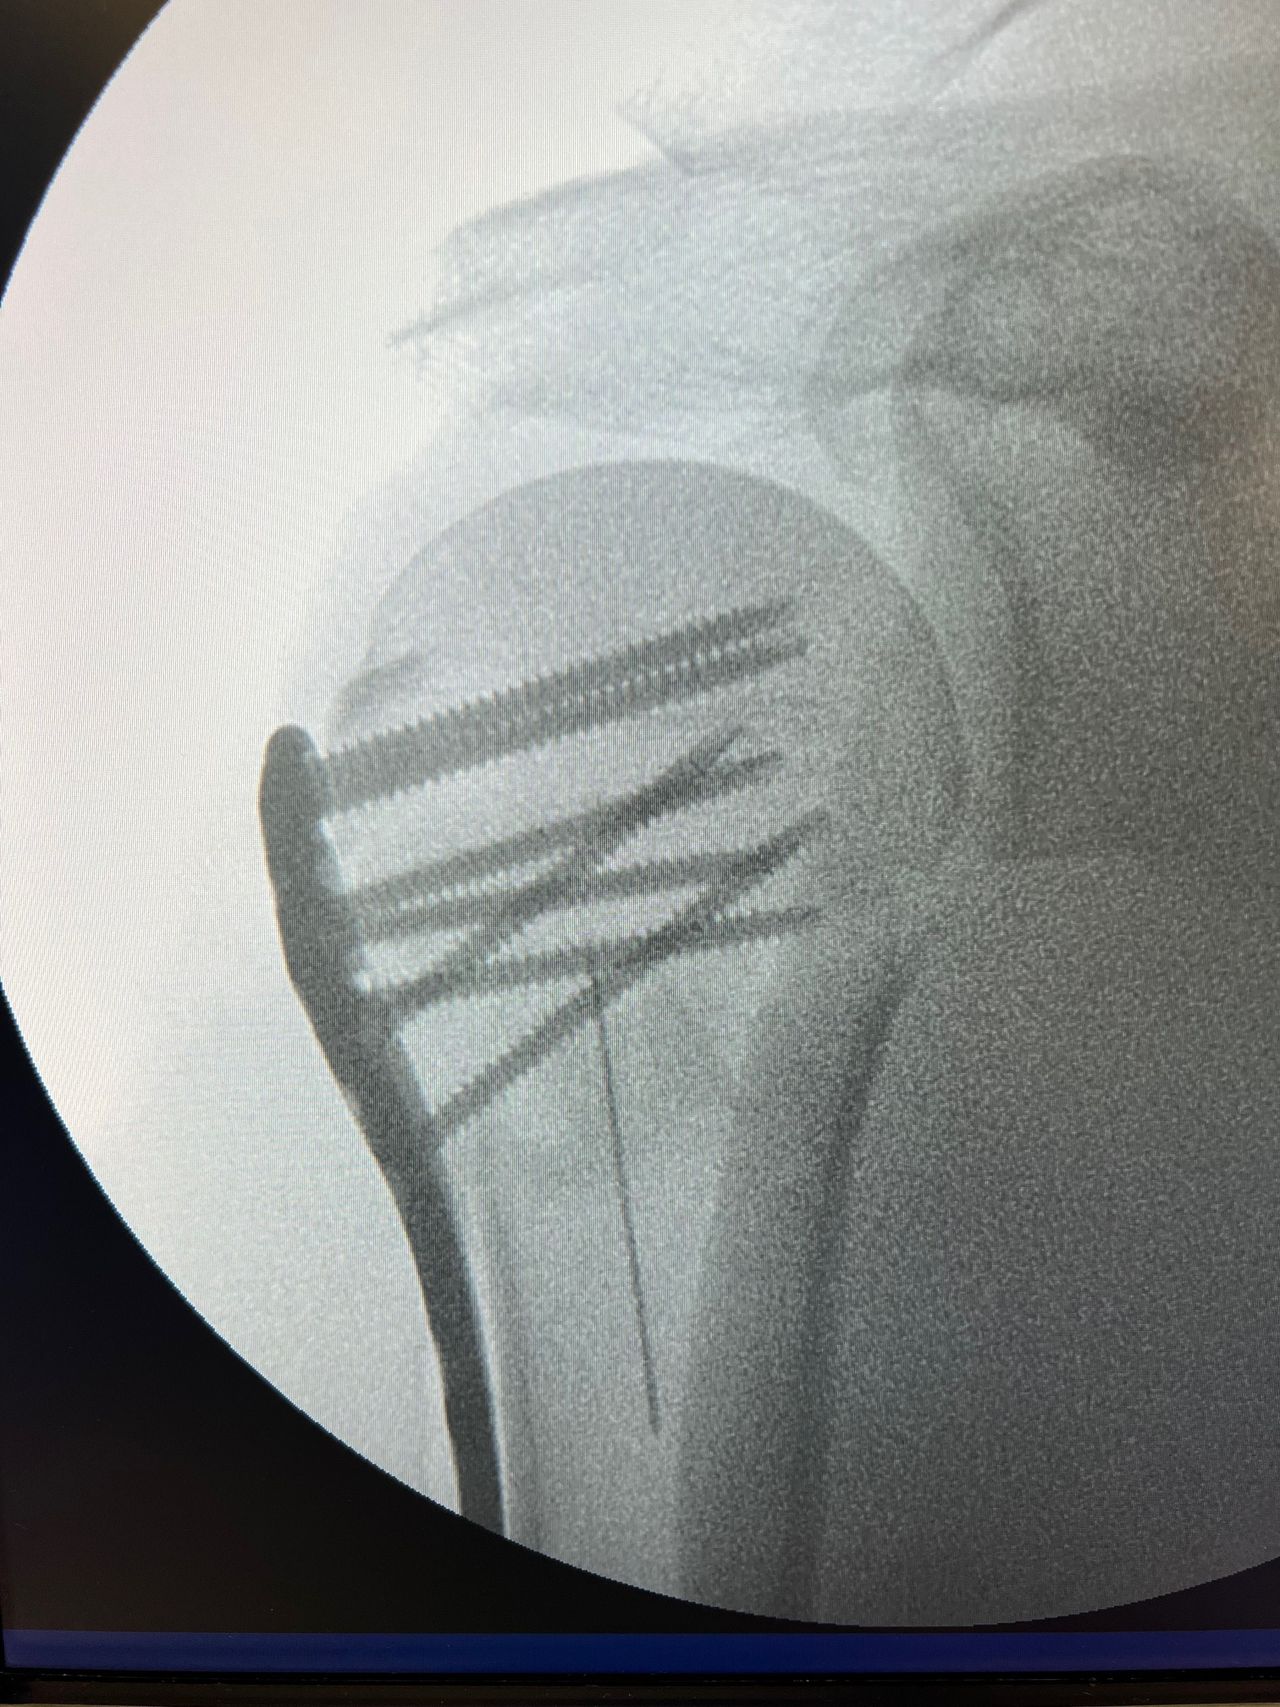

Fotos y vídeos